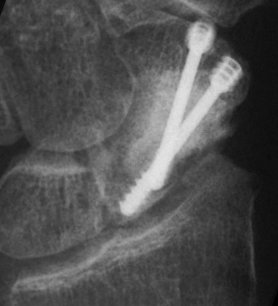

Case 7. This nonunion patient's scaphoid and iliac crest were unusually soft bone.

Click for larger image

After two screws, the fixation was clearly inadequate, so I put a third screw through the graft into the proximal pole. I wasn't sure whether to buy

stock in Herbert screws or Zantac. The fracture healed despite AWOL and no immobilization.